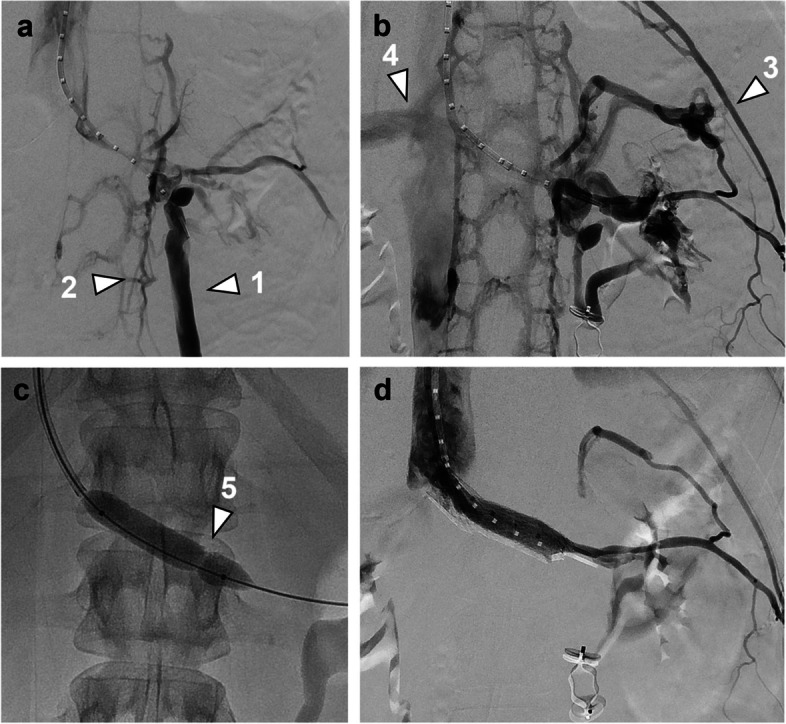

The optimal management strategy of nutcracker syndrome is debated, especially in the setting of concurrent pelvic congestion syndrome. In this article, we describe our treatment algorithm as illustrated by four different case scenarios. In our experience, renocaval pressure gradients are often inconclusive, but evaluation of the left renal vein waveform as well as a "test PTA" with evidence of a waist in the balloon can be helpful in unmasking a relevant stenosis. We consider nutcracker syndrome not to be a contraindication for ovarian vein embolization. Decision for simultaneous or sequential stenting should be based on angiographic findings and clinical course.